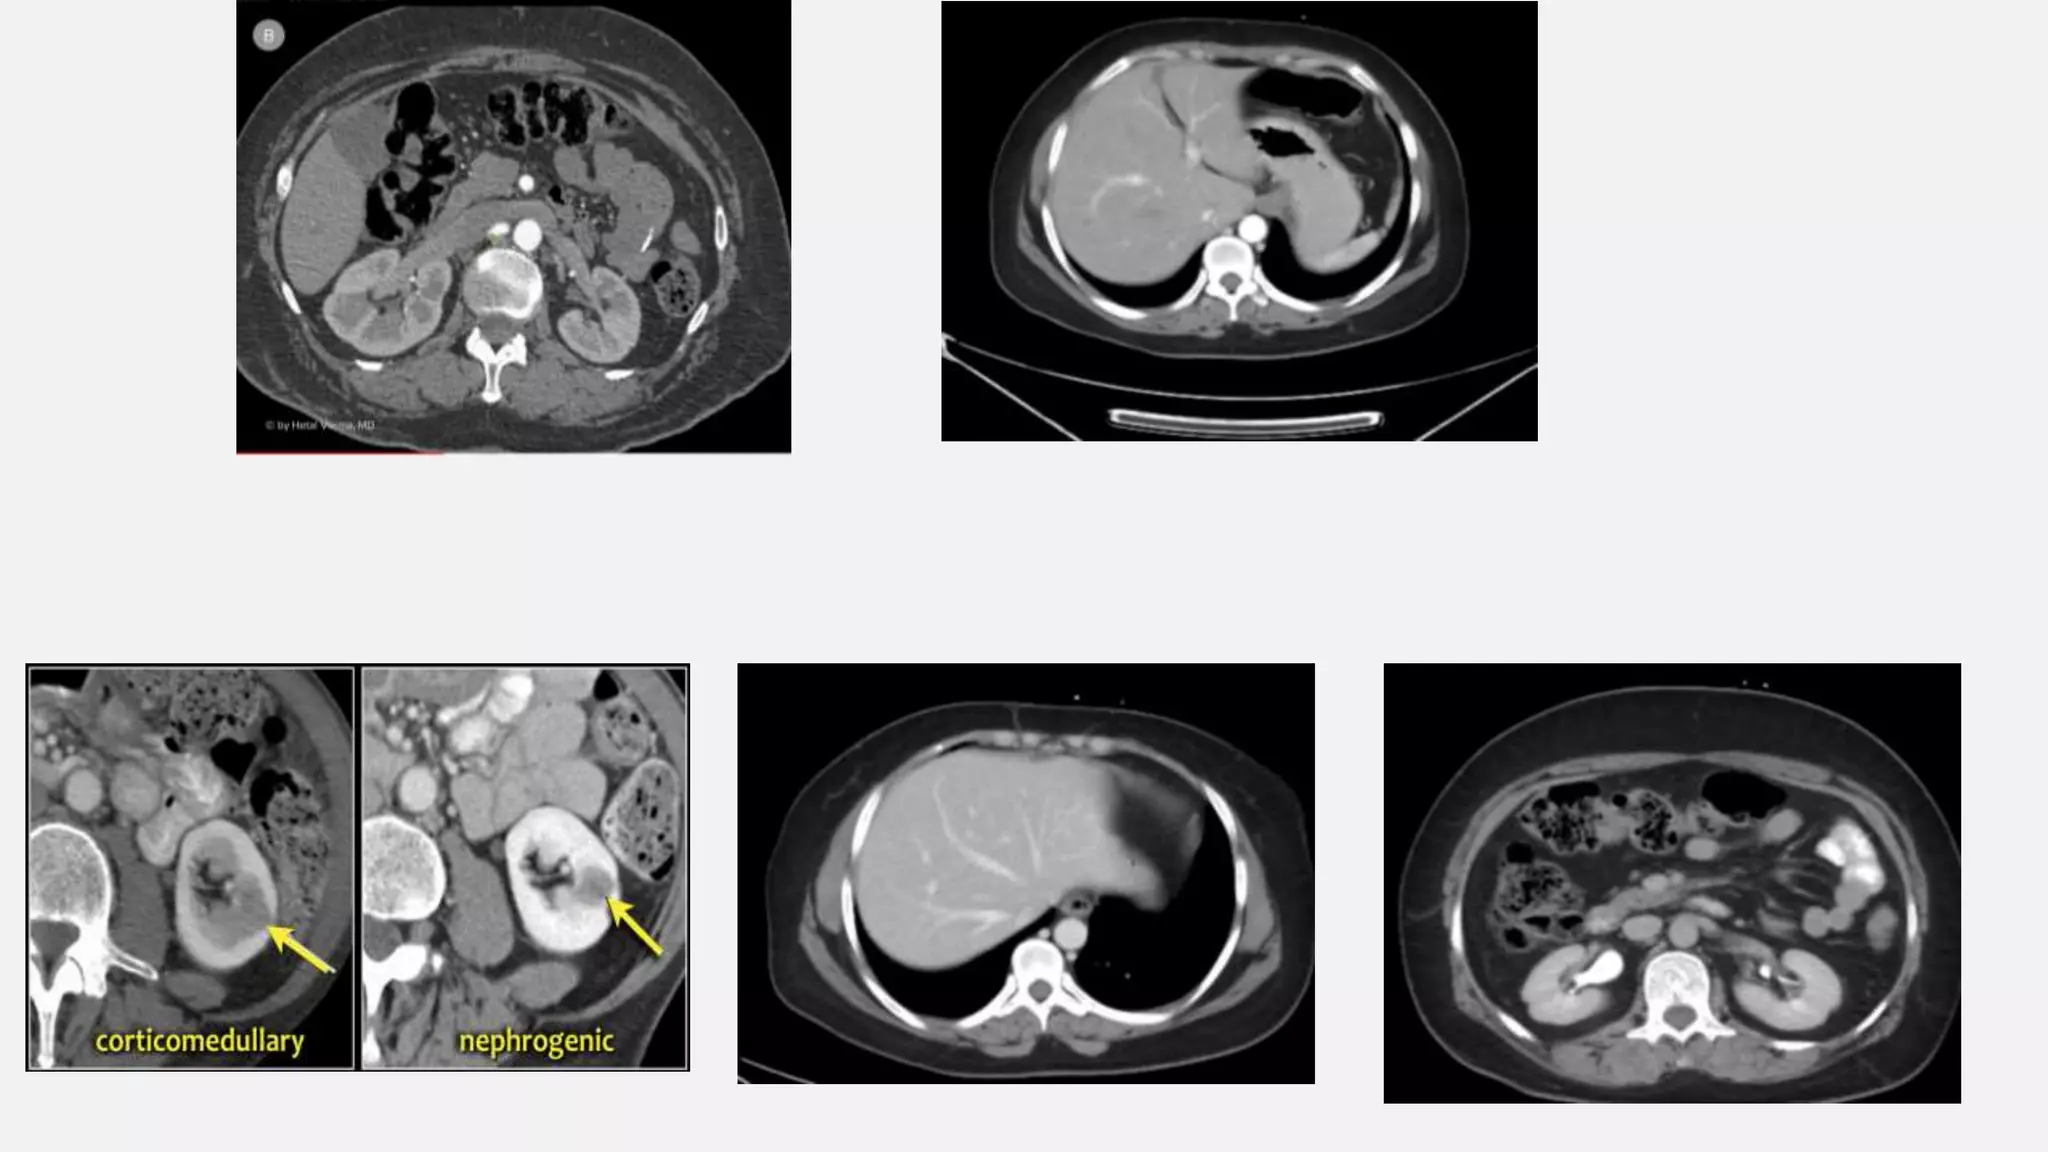

NEPHROGENIC PHASE ENHANCEMENT OF: ALL RENAL PARENCHYMA INCLUDING MEDULLA

• #33 70-80 sec p.i. or 50-60 sec after bolustracking. Although hepatic phase is the most accurate term, most people use the term "late portal phase". In this phase the liver parenchyma enhances through bloodsupply by the portal vein and you should see already some enhancement of the hepatic veins.

• #34 - 100 sec p.i. or 80 sec after bolustracking. This is when all of the renal parenchyma including the medulla enhances. Only in this phase you will be able to detect small renal cell carcinomas.

• #38 In the late arterial phase at 35 sec hypervascular lesions like HCC, FNH, adenoma and hemangioma wil enhance optimally, while the normal parenchyma shows only minimal enhancement. Hypovascular lesions like metastases, cysts and abscesses will not enhance and are best seen in the hepatic phase at 70 sec p.i. Fibrotic lesions like cholangiocarcinoma and fibrotic metastases hold the contrast much longer than normal parenchyma. They are best seen in the delayed phase at 600 sec p.i. This late enhancement is comparable to what is seen in cardiac infarcts in MRI of the heart.

• #39 Liver cirrhosis with ascites. Two hypervascular enhancing liver lesions in the arterial phase. Both lesions reveal washout in the portal venous & equilibrium/delayed phases (= hypodense as compared to other liver parenchyma), consistent with HCC.